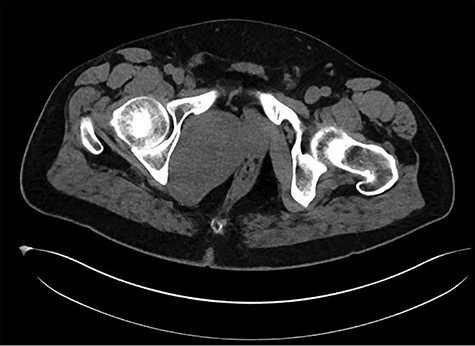

A healthy 47-year-old male with past medical history significant only for hypertension and nephrolithiasis presented to Englewood Health Medical Center in October 2019 with right flank pain radiating to the pubis, hematuria, hard stool with straining and fifteen pound weight loss over 6 months. On physical examination, multiple café au lait spots, small neurofibromas on his trunk and arms and axillary and inguinal freckling were observed. On CT scan, he was found to have a 10.1-cm soft tissue mass in the right hemipelvis and a nephroureteral stent with a 3-mm stone in the proximal right ureter (Fig. 1). Further history revealed the patient had a known pelvic mass discovered on CT approximately 10 years prior (Fig. 2), which was again observed on CT in June 2019 during a hospitalization for nephrolithiasis at Hackensack University Medical Center (Fig. 3); he had been lost to follow-up.

HUMC 6/1/19: 9.7 × 6.3 × 7.5-cm-sized right pelvic wall soft tissue mass.